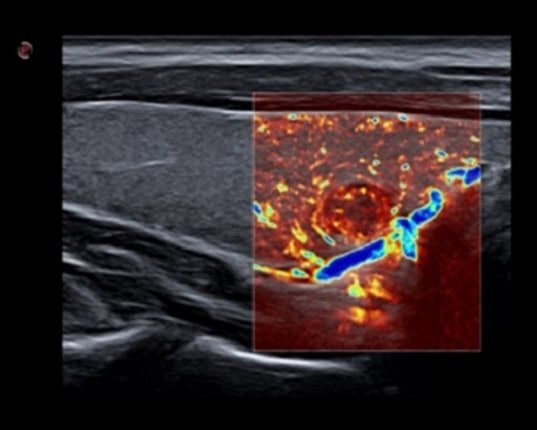

Siêu âm tổng quát

MicroV – Siêu âm vi mạch máu: Nhận diện các dòng chảy siêu nhỏ và vận tốc thấp, đặc biệt phân bố mạch máu trong các sang thương khu trú.

may sieu am mylab x7